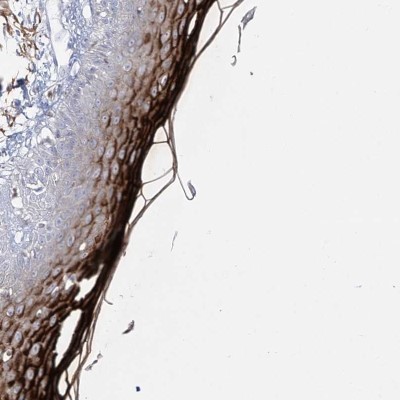

- Main image

- Experimental details

- Immunohistochemistry-Paraffin: Dermokine beta Antibody [NBP1-86840] - Staining of human vulva/anal skin shows strong cytoplasmic positivity in squamous epithelial cells.